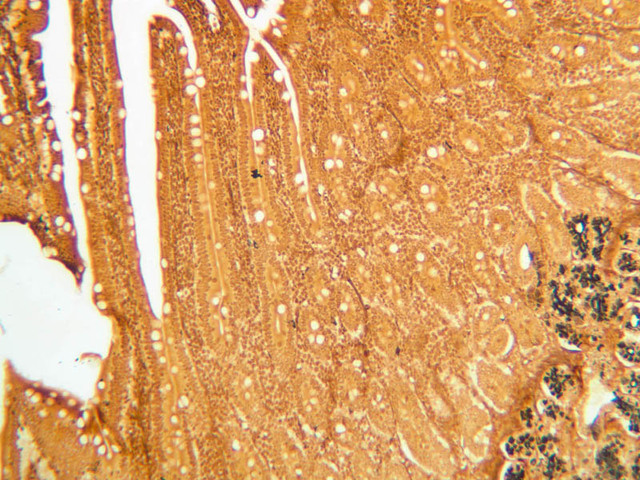

The glands of the stomach exhibit regional variations in size, form, and cellular composition. The glands of the cardia (slide B-1) and pylorus (slide B-9) are coiled, often branched tubules that that are associated with very deep gastric pits and consist almost entirely of mucous-secreting cells. In the gastric fundus (slide B-4, H&E [2.5x, 10x, 20x, 40x] [10x, 20x, 40x-labeled] [40x]) and corpus (slides B-5, H&E [2.5x, 10x, 20x, 40x] [10x, 20x, 40x] [40x] & B-6, PAS [2.5x, 10x, 20x, 40x]), the glands are relatively straight and are known as fundic glands or gastric glands; they are made up of mucous neck cells, chief cells, parietal cells, and APUD cells. The lumina of fundic glands are much less evident than are those of cardiac and pyloric glands. Study slides B-4, 5 & 6 to familiarize yourself with the cell types found in fundic glands.

As their name suggests, mucous neck cells are most numerous just proximal to the junction of gastric gland and gastric pit. In H&E-stained sections, these cells, like others which secrete mucous (e.g., goblet cells), tend to stain poorly on account of the loss of their secretory product during histological processing. However, in the section on slide B-6, which has been stained by the PAS technique, they are very easy to identify (bright pink). You should study the distribution of mucous neck cells in this slide and then attempt to identify them in H&E preparations by looking at corresponding regions in slide B-4 or B-5. What functions are served by the mucous-secreting cells of the gastric mucosa?

The chief or zymogenic cells have a rather granular, basophilic cytoplasm and produce pepsinogen, which, upon encountering the acidic gastric juice, is converted into the proteolytic enzyme pepsin. As the name suggests, the chief cells are usually the most numerous cell type in the glands of the fundic region.

The parietal cells are large and have conspicuously acidophilic cytoplasm. They are the source of both gastric HCl. and intrinsic factor, which is necessary for uptake of vitamin B12 in the ileum. The fine structure of parietal cells shows that their cytoplasm is filled with a very large number of surface invaginations or secretory canaliculi, which, in turn, are covered with microvilli. It is apparently this elaboration of surface area that allows parietal cells to secrete large amounts of HCl. Why are parietal cells eosinophilic?

Many organs contain cells that have particular affinity for chromium and silver salts; thus, classical histologists were able to identify chromaffin and argentaffin cells. These cells are now generally known as amine precursor uptake and decarboxylation (APUD) cells. They tend to be rather small cells that show little cytplasmic detail and, thus, appear as clear cells in H&E-stained sections. Most of the APUD cells of gastric mucosa produce gastrin, which is important in the regulation of HCl secretion. Argentaffin cells are identifiable in the sections of pylorus on slide B-11 (Ag [2.5x, 10x, 20x, 40x-labeled]).